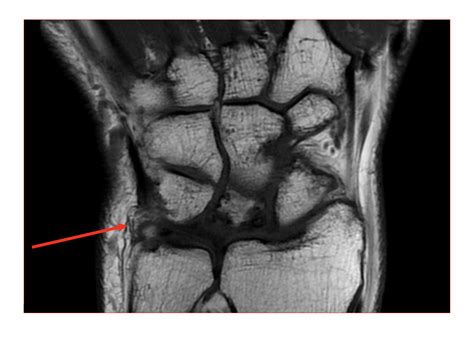

• Ligament and Tendon Injuries: Tears or strains in the ligaments and tendons can be clearly visualized with MRI.

• Arthritis: MRI can show the extent of cartilage damage and bone changes associated with arthritis.

• Description of Findings: A detailed description of any abnormalities, such as fractures, tears, or cysts.

• Diagnosis: The radiologist’s interpretation of the findings, including the likely diagnosis.